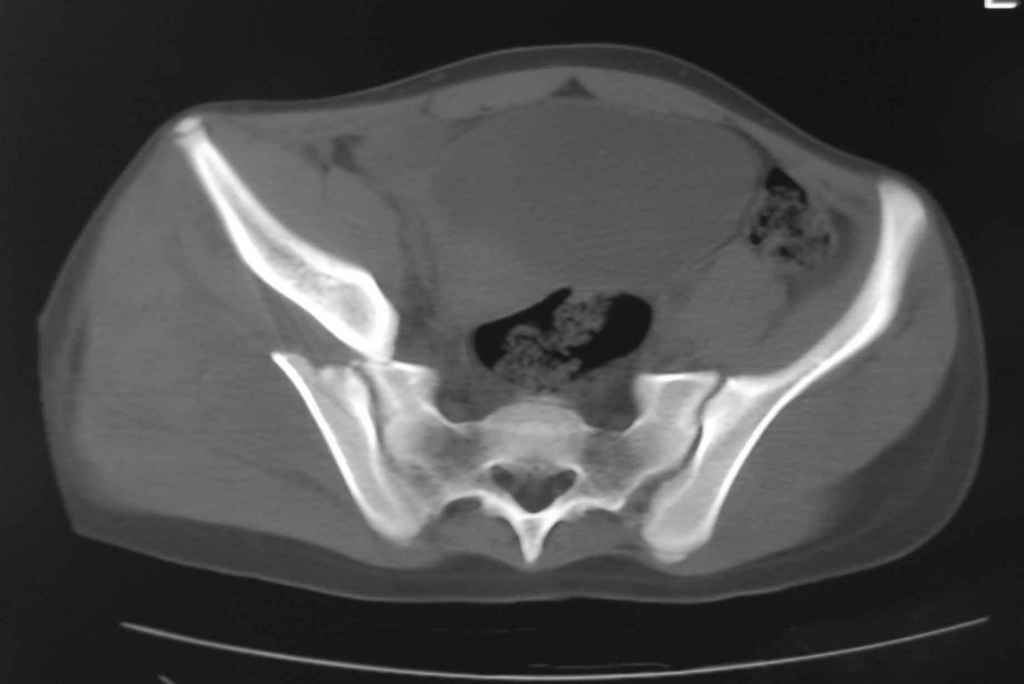

Ребенок 13 лет Перелом костей таза.

Уважаемые коллеги, в нашу клинику поступил ребенок 13 лет; травма четыре дня назад(падение с 5-го этажа). Помогите определиться с дальнейшей тактикой.